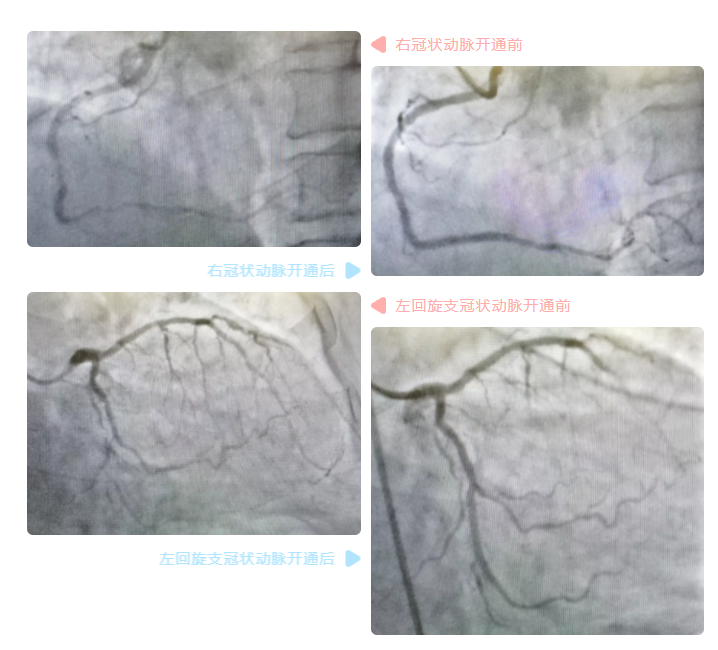

3个小时后,介入手术结束。徐先增团队顺利为罗先生开通了闭塞的右冠状动脉及左回旋支冠状动脉,并分别植入1枚支架,实现了冠脉血流的再通畅。